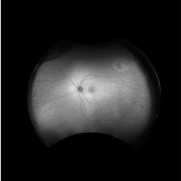

Retina Images (13 files)

Retina Images (13 files)